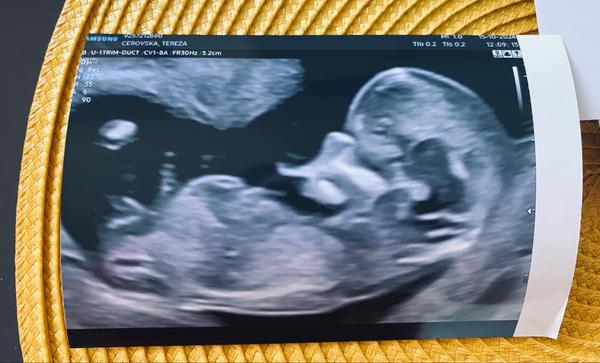

Dokážete odhadnout pohlaví miminka z ultrazvuku?

Ahoj holky, zřejmě dost častá diskuze a otázka. Ale zajímá mě názor “zkušených” rodiček, zda by si dokázaly tipnout na fotce z ultrazvuku pohlaví miminka i u mě? Jde mi jen o tipy, já pohlaví vědět nechtěla a teď jsem tak zvědavá, že se asi pana doktora při příští kontrole zeptám :D

Já holčičku.Vybezek mi přijde rovný a dlouho se ta pipina může jevit jako pindík. Těmi hormony jsou oteklé. A to je jen taková blbost, ale podle tvaru lebky bych taky řekla holčička. No každopádně dej pak vědět , jsem zvědavá zda jsem typla správně 😁

@kaktus092 Je pravda, že ten výběžek nám pan doktor okomentoval, že je u kluka a u holky ještě v tom týdnu stejný a to snad někde v 10tt 😀 dále už jsme nikde nic neviděli. Ale pořád váháme, zda nepočkáme do porodu na překvápko